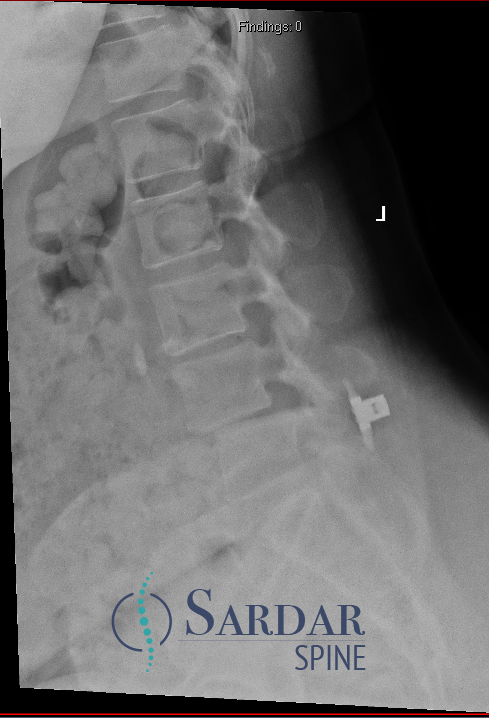

From robotics and AI-driven surgical planning to virtual modeling and custom implants, I’ve embraced a combination of tools that allow me to create tailored surgical plans for my patients—particularly those with scoliosis and spinal deformities.

What sets my approach apart is the seamless integration of these advanced technologies to ensure unparalleled accuracy and better outcomes for each patient.